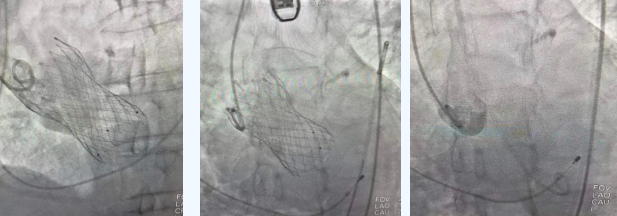

在麻醉手術(shù)中心的配合下,曾廣偉主任用導(dǎo)管經(jīng)股動脈鞘進(jìn)入主動脈瓣目標(biāo)位置,經(jīng)豬尾導(dǎo)管造影可見主動脈瓣大量返流,因左室流出道較寬,大于瓣膜落腳點(diǎn)直徑,瓣膜釋放位置選擇及釋放難度極大。更為關(guān)鍵的是,患者常規(guī)四個錨定點(diǎn)只有一個可以用,定位要極其精準(zhǔn)才能保證瓣膜釋放后牢靠,同時不能有大的殘余瘺!稍有移位可能就需要再次植入瓣中瓣或者開刀!

術(shù)中,曾廣偉主任團(tuán)隊高效配合,完成了特定時間點(diǎn)起搏心臟、臨時短時間關(guān)閉呼吸機(jī)、降低主動脈瓣阻力、快速釋放瓣膜等一系列高難度操作,有效保證瓣膜精準(zhǔn)釋放。瓣膜釋放經(jīng)TEE確認(rèn),主動脈瓣膜釋放位置佳,經(jīng)豬尾導(dǎo)管造影,主動脈瓣返流即刻消失,且無瓣周瘺。